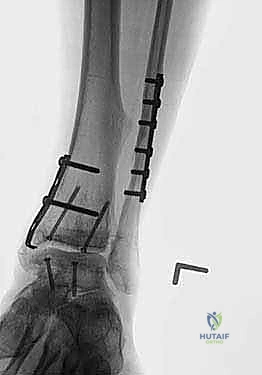

4. Placement and Fixation of the Grafts

Now for the moment of truth – seating our fresh osteochondral allografts.

- Graft Seating:

- With the ankle held in a position of plantarflexion, carefully introduce and seat the prepared tibial allograft onto the resected tibial plafond. Ensure it sits flush and stable.

- Next, introduce and seat the talar allograft onto the resected talar dome.

- Remove External Fixator and Assess Stability: Once both grafts are initially seated, we can carefully remove the external fixator.

- Now, gently take the ankle through a full range of motion. Assess for any impingement, instability, or incongruity. The grafts should articulate smoothly and congruently. This dynamic assessment is crucial.

- Fluoroscopic Confirmation of Apposition and Anatomy: